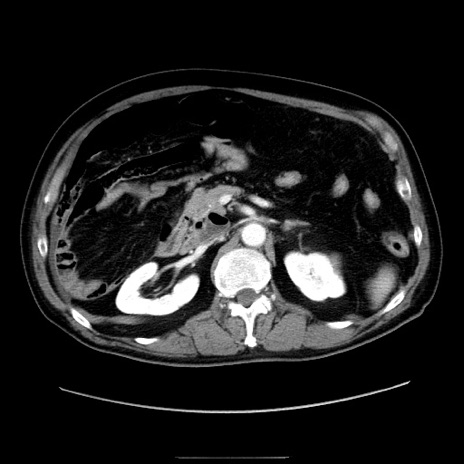

症例30(横断像)

冠状断像

【症例】80歳代男性

【主訴】臍周囲痛

【現病歴】約6時間前から臍下部痛が出現。次第に腹部膨隆・背部痛も生じてきたため来院。背部痛の場所は変化しない。

【既往歴】腎盂腎炎

【身体所見】意識清明、BT 36.3℃、BP  131/87mmHg、P 87bpm、SpO2 100%(RA)、臍周囲自発痛・圧痛あり、反跳痛なし、自発痛部位に一致して板状硬あり、腹部膨隆、腸雑音減弱、CVA tenderness両側陰性。

【データ】WBC 19600、CRP 0.33